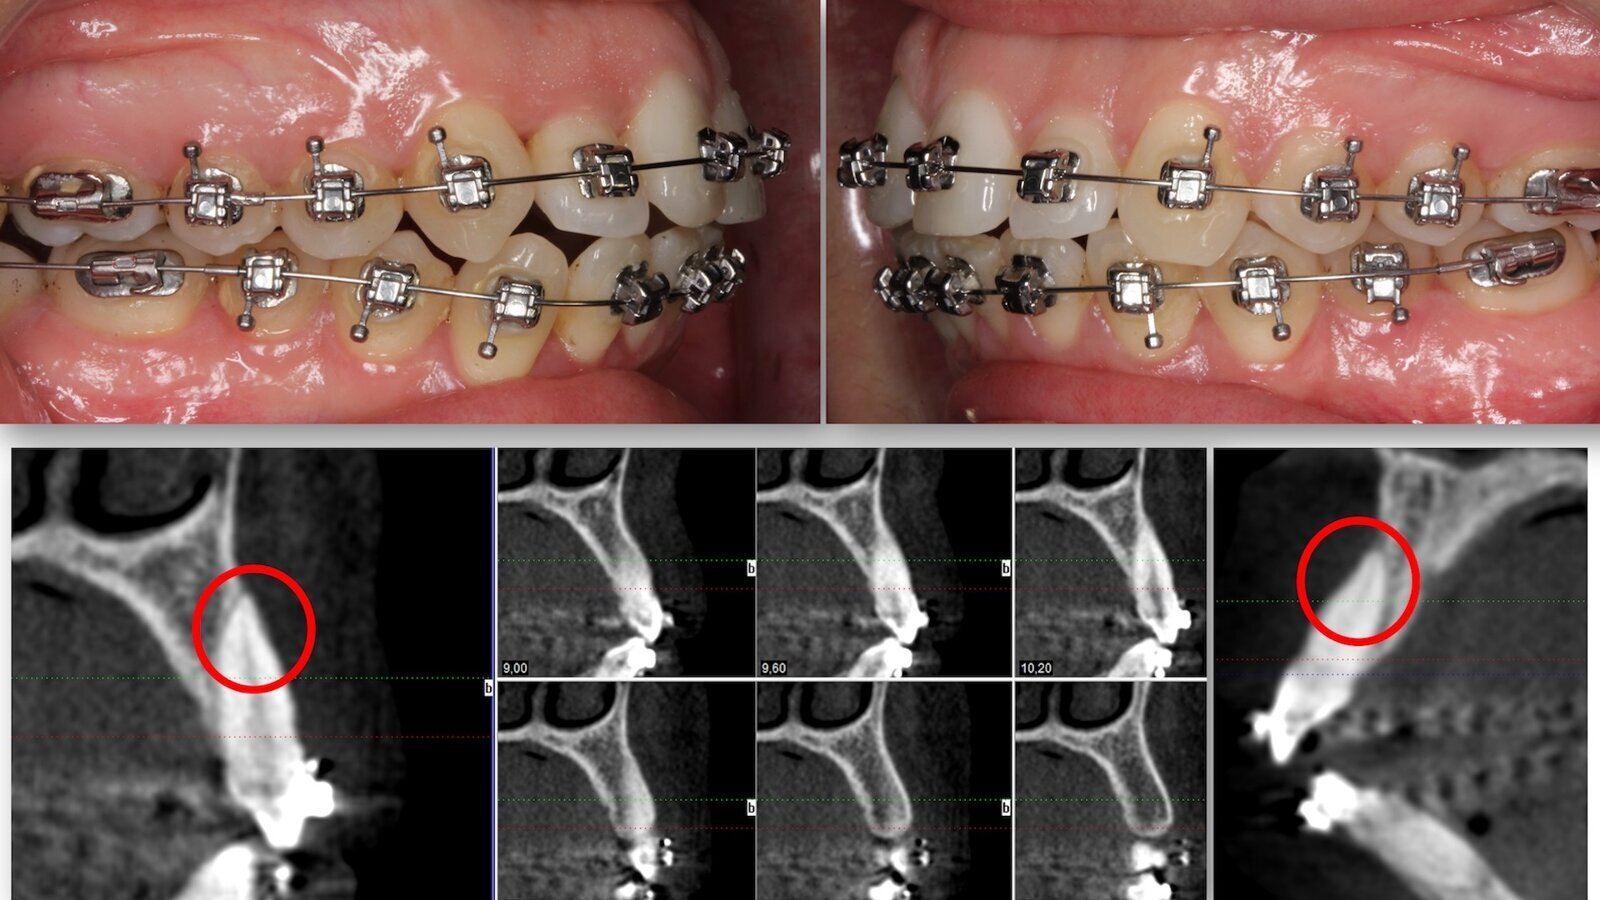

La edad no perdona y el hígado menos, y ya no me compensa sobrepasarme una noche incluso aunque se trate de un magnífico Albariño o un Vega Sicilia Único de 2004, la resaca es ineludible. En el tema que nos ocupa ocurre igual, tras la fiesta de la expansión puede venir la resaca de las tres “R”: Recesión, Reabsorción y Recidiva. Ahora la cuestión es saber quién va a pagar los desperfectos de la fiesta y quiénes, con su agresivo marketing, alentaron a la joven ortodoncista a producir tal desastre. La situación, como evidencia el CBCT, es harto complicada porque estamos hablando de un grave compromiso periodontal que cuestiona la supervivencia de la dentición de esta joven paciente, y su salud oral a medio plazo. Explicarle lo que el CBCT evidencia es muy doloroso y, lo peor, es no poderle ofrecer ni un tratamiento ni una solución que no esté rodeada por una niebla de pesimismo. Creo que gran parte de los compañeros rechazarían el retratamiento del caso por los riesgos que se han de asumir (extracción de cuatro premolares, control estricto del anclaje, marcadas torsiones positivas para intentar meter de nuevo las raíces en el espacio óseo medular, movimientos dentarios con fuerzas ligeras) y por tener delante un paciente quemado. Son casos que acaban con un claro perjuicio legal y económico para el profesional.

Figura 8. El retratamiento de la paciente anterior, como Tweed hizo con alguno de los casos de su Maestro, comprendió la exodoncia terapéutica de los premolares y la torsión positiva de la mayoría de los dientes intentando meter de nuevo las raíces en la medular, alejándolas en lo posible de la cortical.